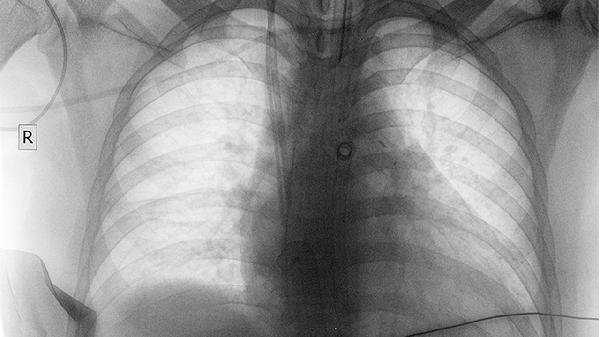

45岁以上吸烟者建议每年做一次低剂量螺旋CT检查,这是目前最有效的早期筛查手段。